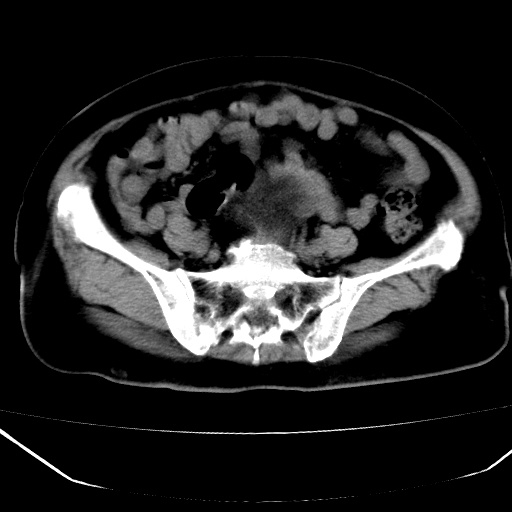

患者,女,74岁,无不适,b超示盆腔包块。

子宫前上方巨大脂性肿物,肿物边缘为较厚软组织密度影,其内缘欠光整,脂性密度中央见结节状软组织密度影“漂浮”,肿物与子宫前壁关系密切,考虑1脂肪瘤2皮样囊肿3肌瘤脂样变

ct值-90hu